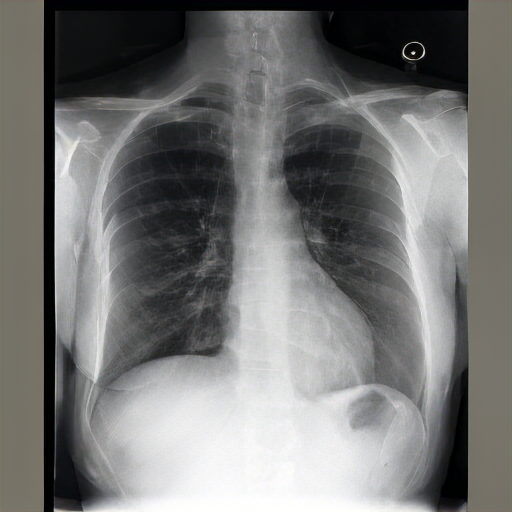

The lungs are well expanded and appear clear. Cardiomediastinal silhouette and hilar contours are otherwise unremarkable. No pleural effusion, or pneumonia pneumothorax. IMPRESSION: No acute cardiopulmonary process or evidence of traumatic injury or acute aortic abnormality are. Consider CT to be in etiology and sensitivity for fractures.